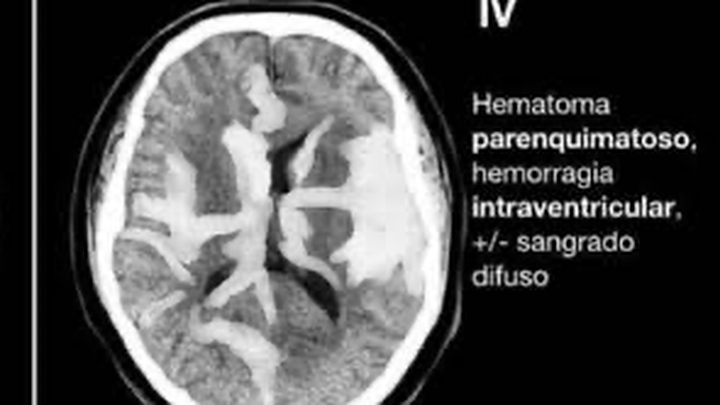

Hola, Me llamo Gus y mi mamá sufrió de una hemorragia cerebral fisher IV a raíz de una ruptura de un aneurisma cerebral, por lo que solicito su ayuda para alcanzar a cubrir los gastos que de esto conlleva.